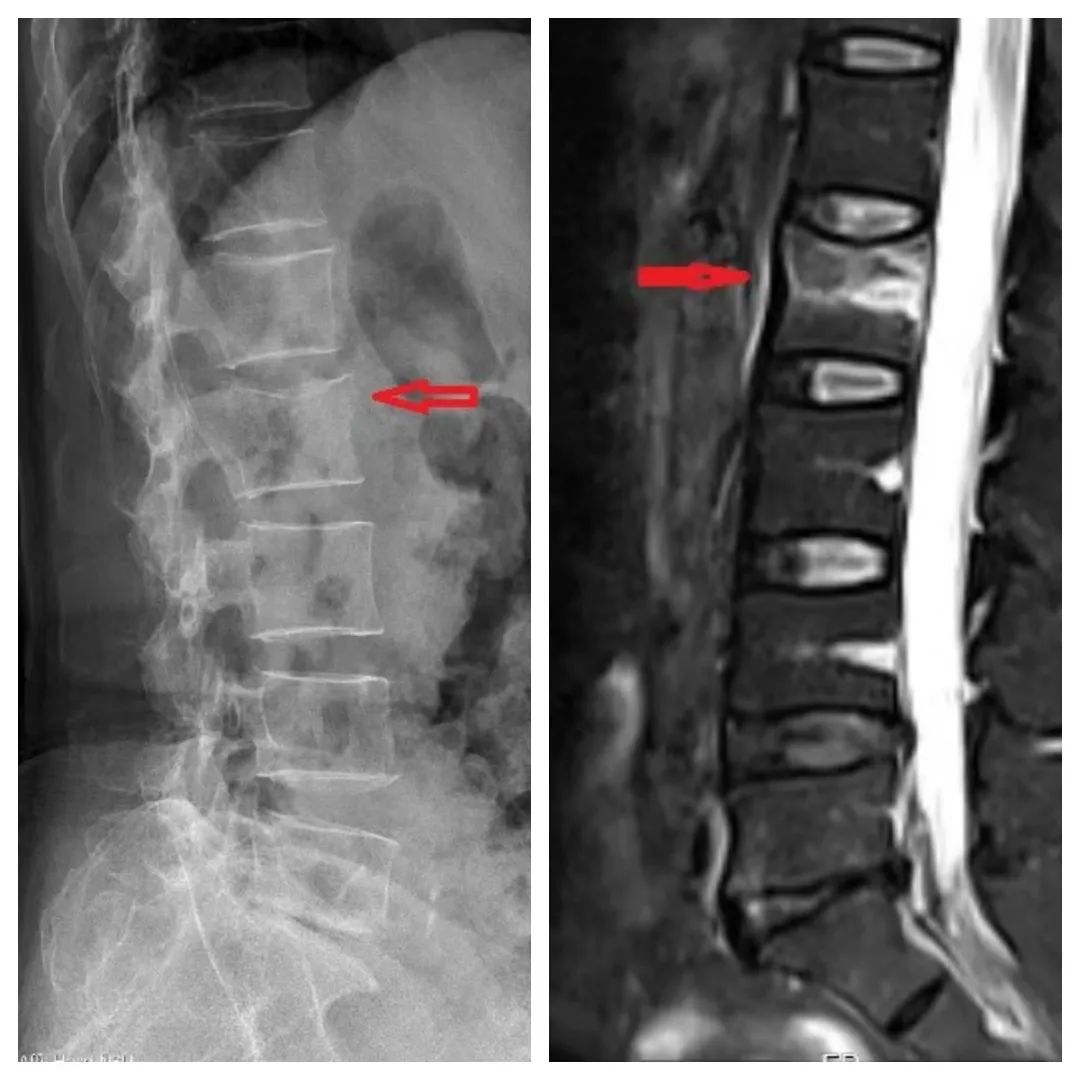

丁阿姨的X片(左)、磁共振(右),提示腰2椎体骨折

家人赶紧将其送到医院。经检查,确诊为脊柱腰2椎体发生压缩性骨折。